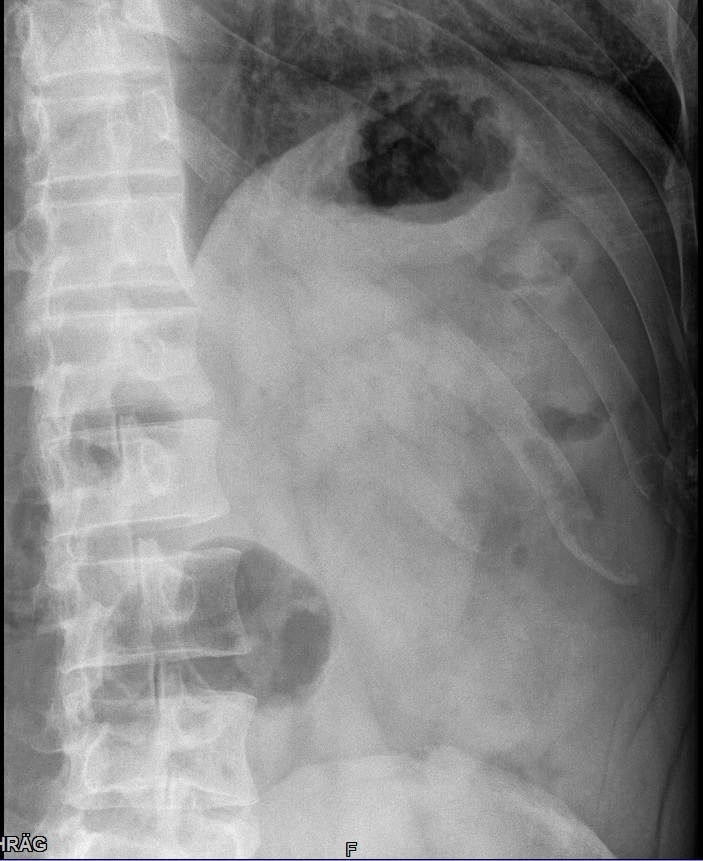

Fehler

Rippen 7-9 werden vom Kassettenrand abgeschnitten. Eine Beurteilung ob die Kortikalis intakt ist, kann hier nicht getroffen werden.

Abhilfe

Patient besser auf der Kassette lagern und schauen, dass beim Atemkommando nicht die Rippen über die Kassette ragen. Sollte das alles nichts bringen evtl. auch auf eine größere Kassette zurückgreifen.